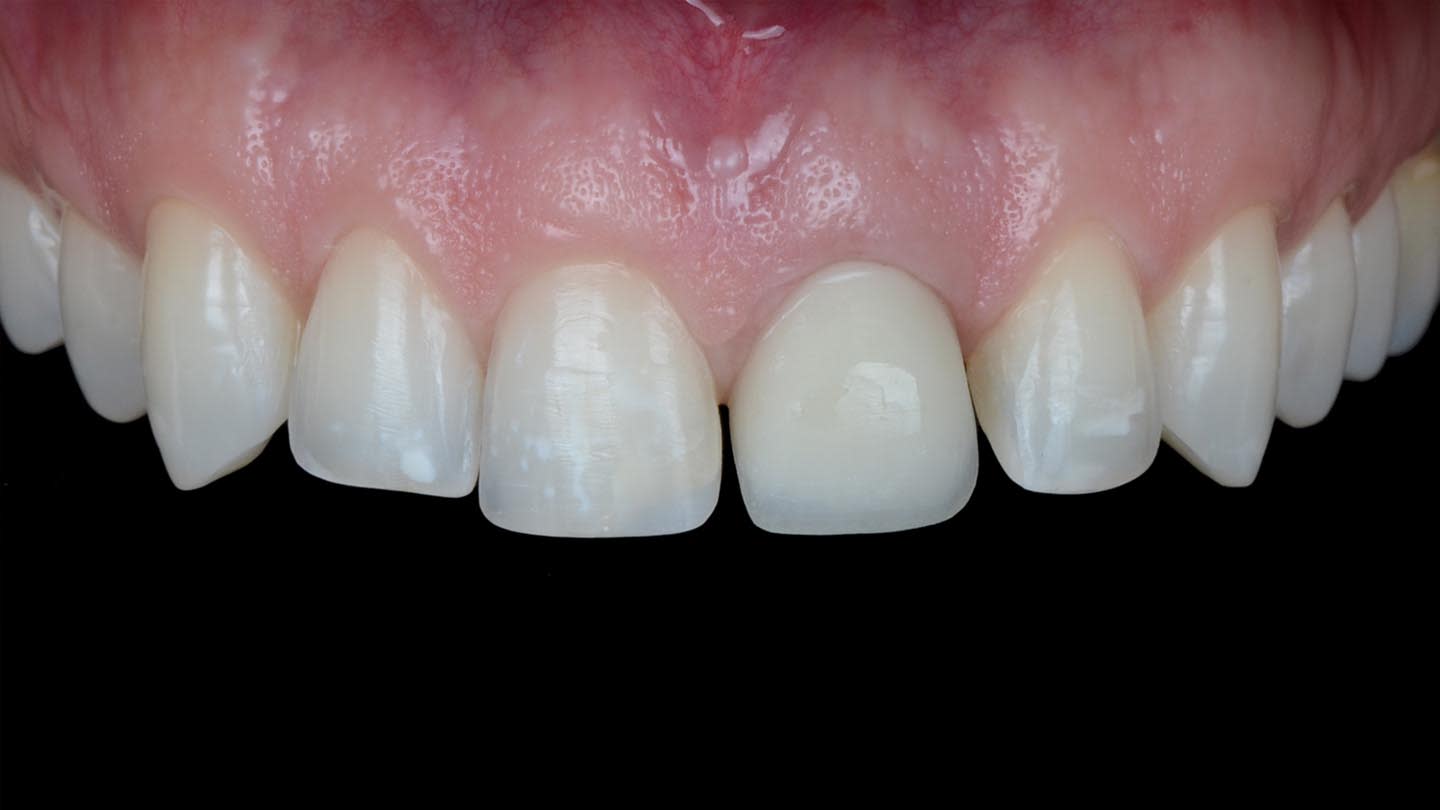

A 40-year-old male patient presented to the author’s (MR) office with the request to improve the esthetics of his smile, as there were several extensive infiltrated composite restorations and a chipped crown showing a severe dark color on an endodontically treated tooth (Figure 1 and Figure 2).

After the luting procedure was completed, a water-based gel was applied to the margins of the restorations to eliminate the oxygen-inhibited layer, and then light-curing was performed for 60 seconds on each veneer. Centric and eccentric contacts were verified using articulating paper. The final results demonstrated the integration of the restorations with natural texture and morphology and an accurate shade matching (Figure 18 and Figure 19). Based on the authors’ experience, these procedures are best performed under magnification.